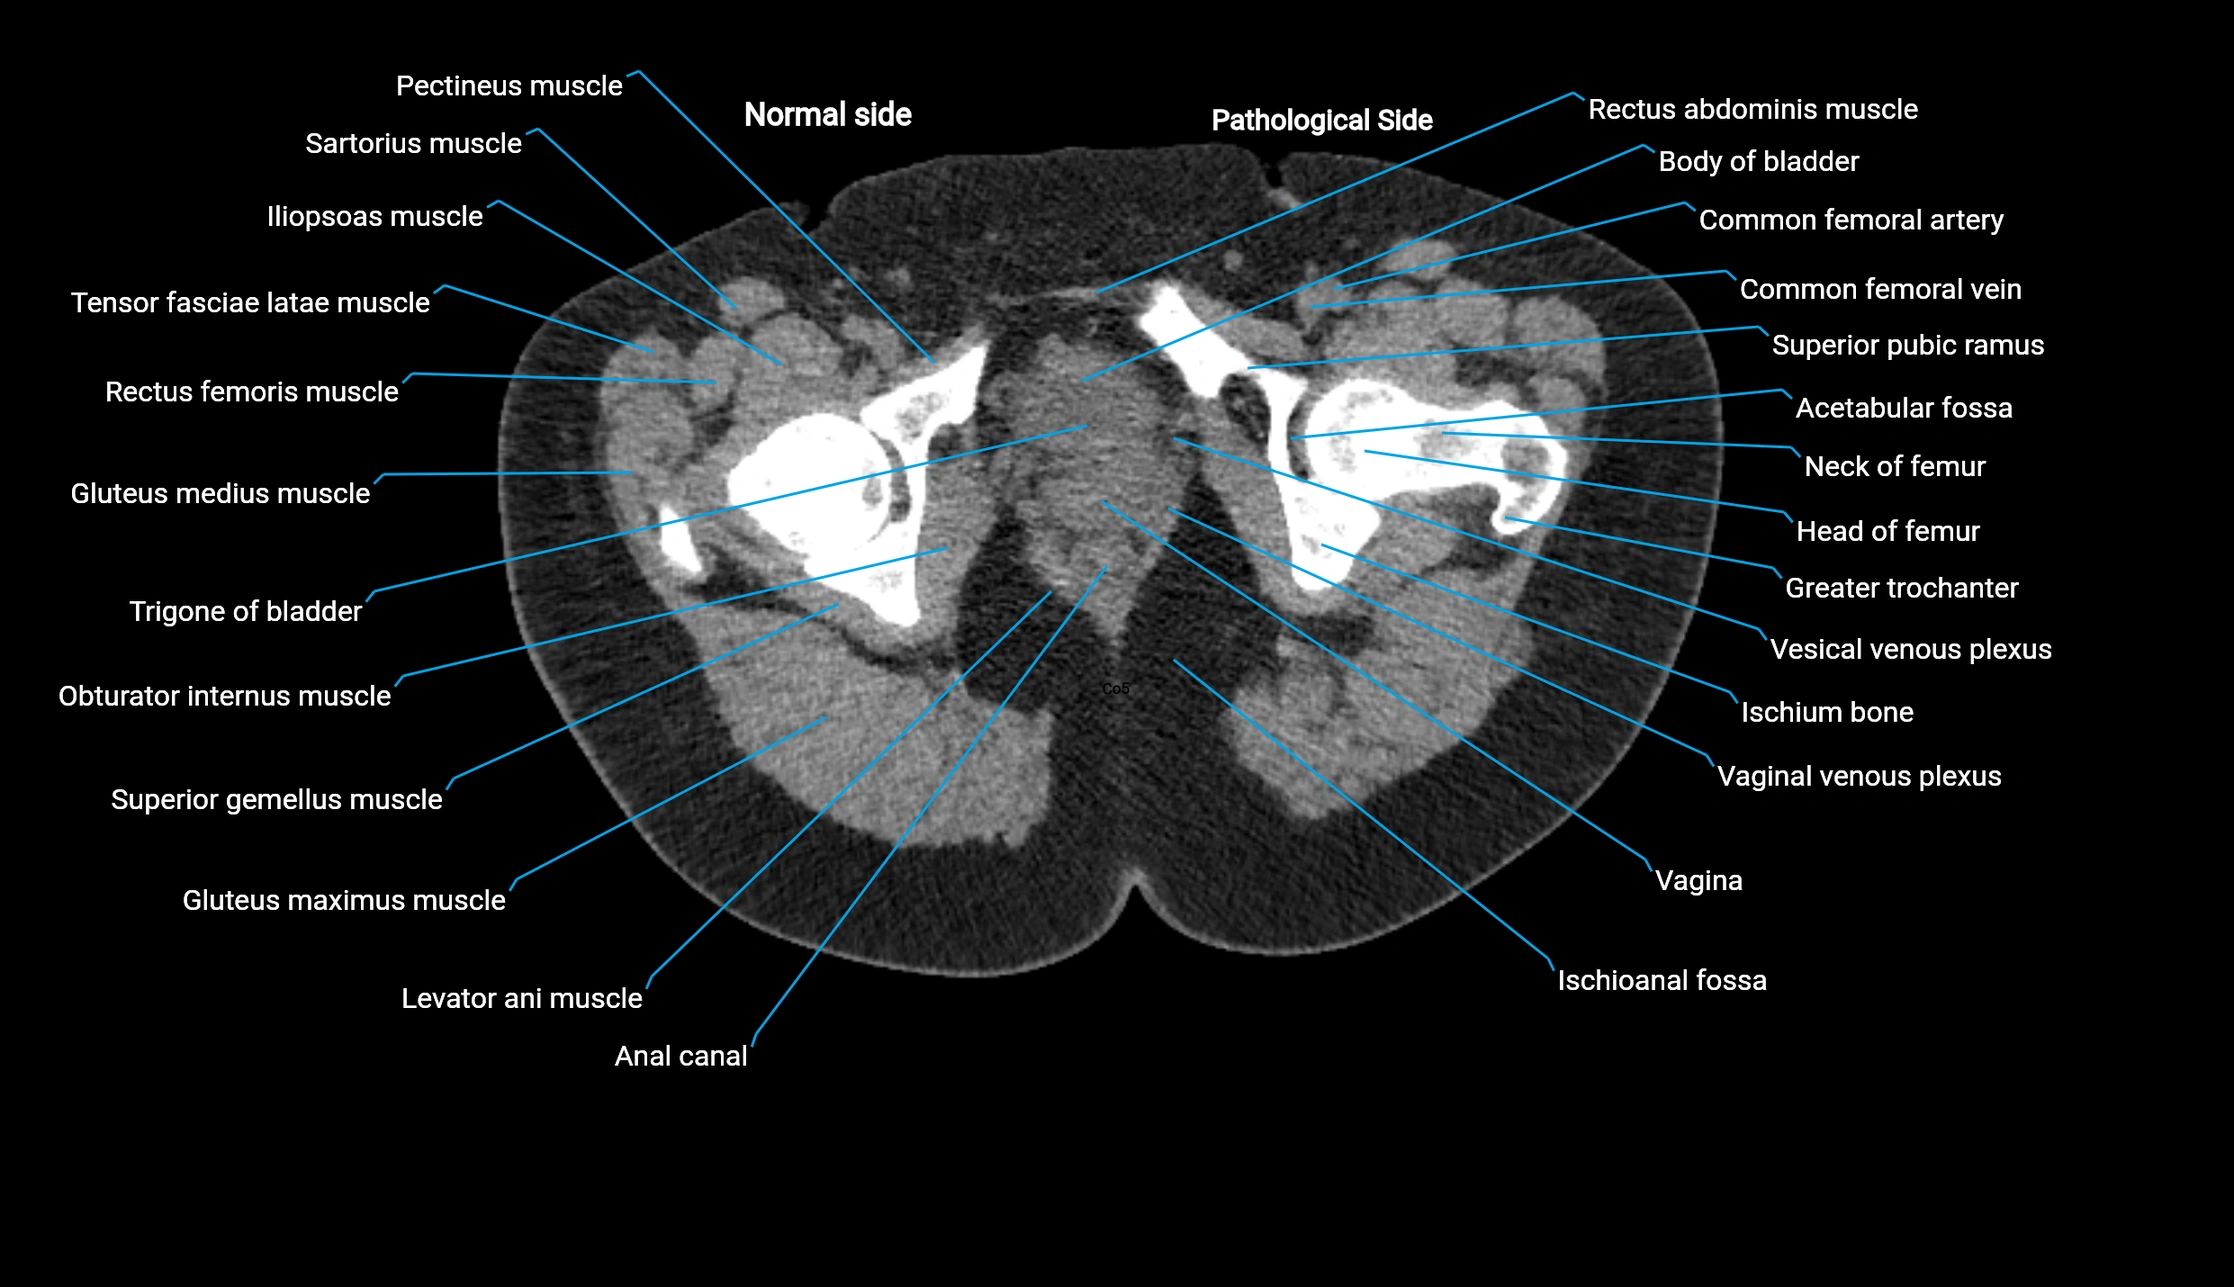

CT VRT 3D image

image